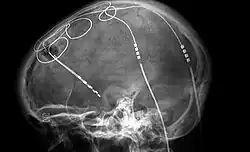

X-ray image of deep brain stimulation, an experimental procedure used to treat disorders such as OCD and depression.